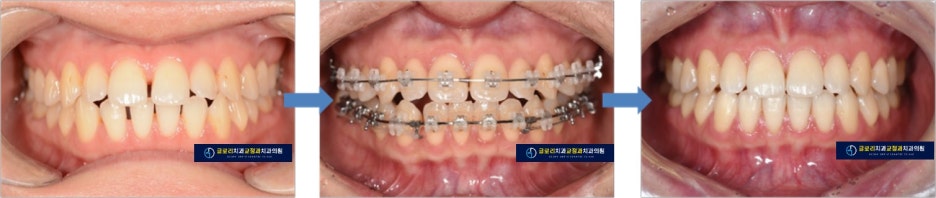

1) 정면/측면 사진

사진에서 보면 곳곳에 공간이 있는 것을 알 수 있습니다.

어금니쪽 관계는 1급 관계로 정상입니다.

배열 상의 문제는 크지 않았기 때문에 간단한 배열 후 공간 모으기 과정을 통해

1년 이내의 교정 치료 기간으로 치료를 마무리 하였습니다.

예상했던 것 보다 기간도 짧고 공간이 잘 닫혀서

환자분께서 매우 만족하셨습니다.